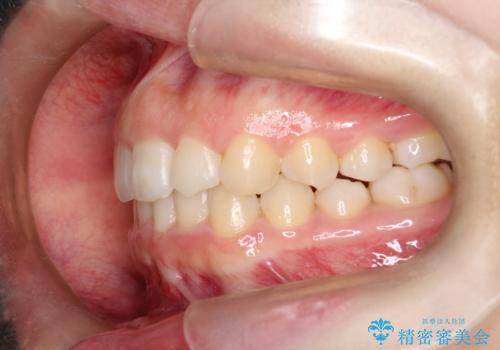

押しつぶされた歯列、アーチの拡大だけで非抜歯で改善した症例

強い叢生がありましたが、抜歯は行わず上下顎ともに、主に歯列弓の拡大を行い叢生を改善しました。

見た目、嚙み合わせ及び、治療期間や施術内容に大変ご満足いただきました。